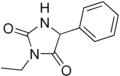

On appelle hydantoïnes les dérivés substitués de l'hydantoïne. Ces composés ont des propriétés relativement similaires à celles des imidazolidines, les dérivés saturés des imidazoles. Elles sont utilisées en pharmacie comme antiépileptiques. On peut notamment citer parmi les composés pharmaceutiques de type hydantoïne :

- l'éthotoïne ;

Éthotoïne

Éthotoïne Phénytoïne